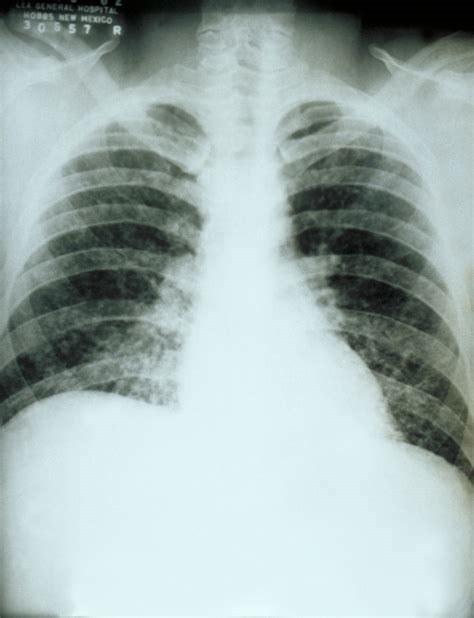

Distributed under CC BY-SA 4.0, from Wiki, without modification.

Chronic cavitary pulmonary histoplasmosis refers to progressive cavitation of the lung in those with underlying lung disease. It is usually bilateral and involves the upper lobes. The presentation is similar to chronic pulmonary aspergillosis with productive cough, increasing shortness of breath, weight loss, night sweats and sometimes fever.